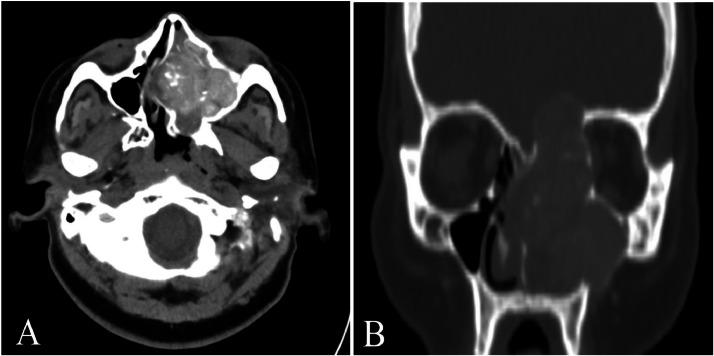

酷似假瘤的慢性侵袭性真菌性鼻窦炎:一例报告。

Chronic invasive fungal sinusitis mimicking pseudotumor: A case report.

Fungal sinusitis encompasses a wide range of diseases, including both invasive and noninvasive, acute, and chronic forms. The incidence of invasive sinusitis is on the rise, primarily affecting immunocompromised individuals and diabetics. This case report highlights a patient who developed invasive fungal sinusitis despite no other apparent cause of immunosuppression. Imaging studies suggested the diagnosis, confirmed by presence of on mycological culture.

摘要

真菌性鼻窦炎涵盖多种疾病,包括侵袭性和非侵袭性、急性和慢性形式。侵袭性鼻窦炎的发病率正在上升,主要影响免疫功能低下的个体和糖尿病患者。本病例报告重点介绍了一名患者,该患者尽管没有其他明显的免疫抑制原因,但仍患上了侵袭性真菌性鼻窦炎。影像学检查提示了诊断,真菌培养发现真菌确诊。